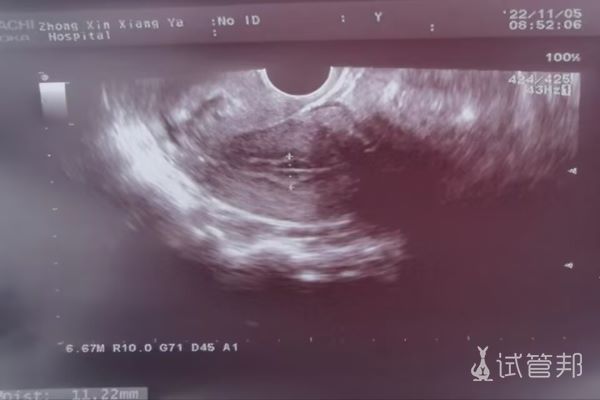

10.30到广西壮族自治区人民医院挂号,然后31号开始抽血(10管免疫检查)然后开始检测卵泡,直至11.7号才排卵,排卵当天做了内膜容受性B超,结果咱也看不懂,跟医生彼此之间的默契,她不说咱也不问,安排11.14号轻刮术+一些免疫检查(抽血)+内膜容受性B超。